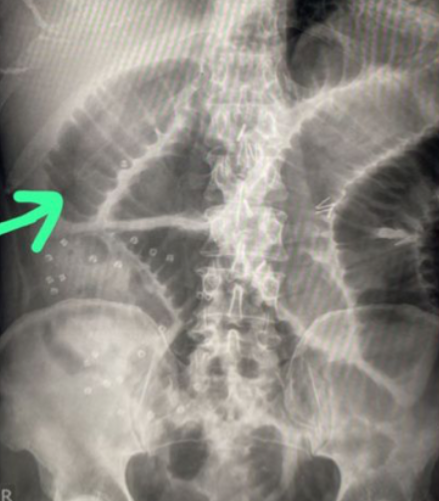

Large bowel obstruction

1- What is imaging technique? X-ray

2- what is your findings? Dilated + obstructive intestine

Mention 4 causes of this condition? Neoplasm, volvulus, polyp, hernia, adhesions, intussusception

Small bowel obstruciton

Q1- Write the name of this imaging and what is your finding?

- plain film air fluid level

- small bowel obstruction with coin sign (valvulae conniventes)

Dx: Mesenteric ischemia (with small bowel necrosis)

Causes:

- Arterial embolus,

- Arterial thrombosis,

- Venous thrombosis,

- Polycythemia

Intra operative management:

- Embolectomy,

- Thrombectomy,

- Bowel resection,

- Vascular bypass, Endarterectomy